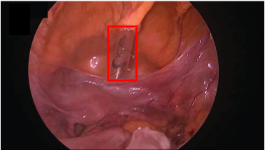

Refer to caption

((a)) Instrument flare

((b)) Partial occlusions by blood

((c)) Smoke-induced occlusion

((d)) Underexposed regions

((e)) Motion blur

((f)) Multiple instruments

((g)) Partial occlusion by organ

((h)) Transparent instrument

Figure 7: Key challenges in surgical video analysis include photometric artifacts (e.g., blurriness, specular reflections), occlusions from blood and tissue deformation, limited camera view, and tool similarity. These complexities hinder robust localization and segmentation, emphasizing the need for advanced Foundation Models. Image adapted from (Cerón et al., 2022).

The domain of surgical video analysis presents unique challenges that hinder robust localization and segmentation of surgical instruments, as shown in Fig. 7. Unlike natural images and videos, surgical frames are characterized by high tissue deformations and frequent occlusions caused by the presence of blood and multiple artifacts on the instruments. Photometric artifacts, as identified by (Ni et al., 2020a), can significantly degrade the performance of segmentation models. Some of the additional complexities include: